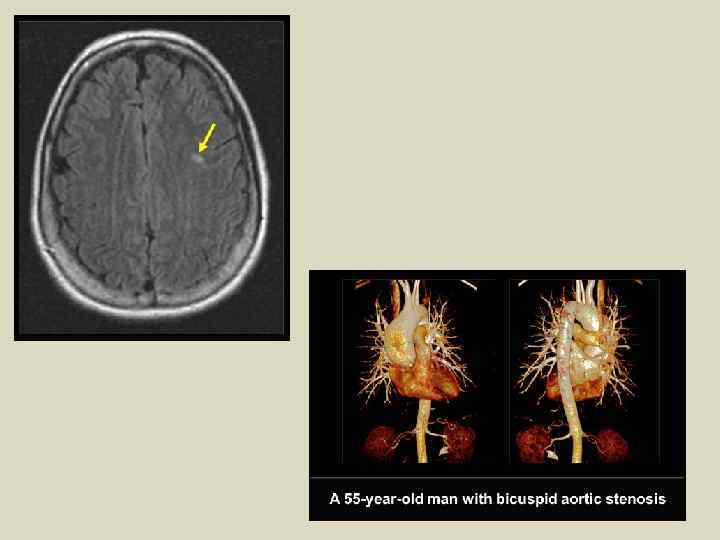

Искусственное контрастирование при КТ: Рентгеноконтрастные йодсодержащие вещества per os или парентерально КТ-ангиография — неинвазивное исследование магистральных сосудов с предварительным в/в контрастированием, которое проводится посредством катетеризации локтевой вены и болюсного введения контрастного вещества со скоростью 3— 4 мл/с при помощи автоматического шприца. Пофазное контрастирование — пофазное изучение органа после болюсного введения в сосудистое русло рентгеноконтрастного вещества. Исследование проводится в три фазы — артериальную, паренхиматозную и венозную в зависимости от времени прохождения контрастом соответствующего звена сосудистой сети.

КТ позволяет реконструировать первичные изображения — получать срезы во фронтальной, сагиттальной и других необходимых плоскостях, а также формировать трехмерные (объемные) изображения. Рентгенологическое исследование кровеносных сосудов, производимое с применением контрастных веществ Артериография Флебография Лимфография

Магнитно-резонансные изображения Головной мозг в двух проекциях МР-ангиография головного мозга